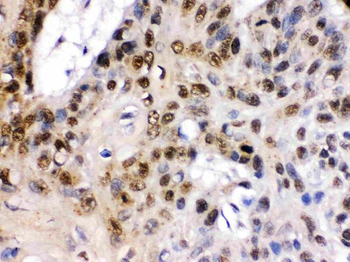

Immunohistochemistry of paraffin-embedded human breast cancer using orb631776 (TCF7L1 antibody) at dilution of 1:100.